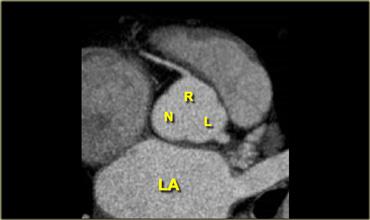

Tái tạo mặt cắt ngang mô tả van động mạch chủ ba lá với lá vành phải, lá vành trái (lần lượt là R và L) và lá không vành (N)

Các lá van của van động mạch chủ được đặt tên theo mối liên quan của chúng với các động mạch vành, cụ thể là lá vành phải, lá vành trái và lá không vành (R, L và N).